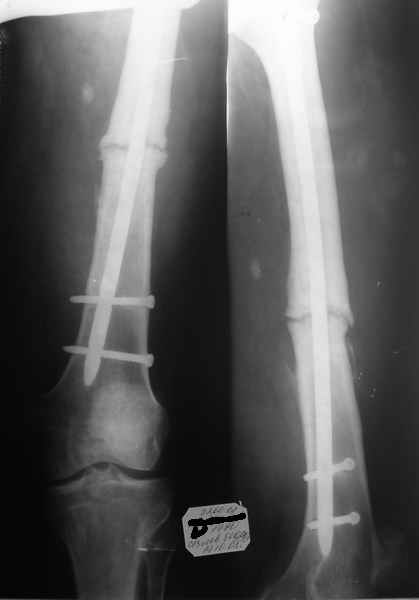

ложный сустав бедренной кости после блокирующего остеосинтеза

Уважаемые коллеги в отделение поступил больной с ложным суставом бедренной кости.

2года назад оперирован по поводу з/перелома с/3 бедренной кости - з/интрамедуллярный остеосинтез с блокированием.Мнения о методах оперативного лечения разошлись.Ваш совет?

Картина нечастая, но иногда встречающаяся, особенно при использовании тонких стержней.

На снимке нет проксимального отдела бедра. Был ли гвоздь динамизирован, если да, то через какое время после операции? Если не был, статический винт сейчас цел?

Лечение подобных несращений (без укорочения, с хорошим контактом, без инфекции) - благодарная задача, и любые существующие методы остеосинтеза способны в конце концов обеспечить сращение: и чрескостный, и накостный, и интрамедуллярный. Поэтому на первый план выходит "цена" результата в виде травматичности, трудоемкости, длительности последующего лечения, риска неудач и осложнений и т.д.

Оптимальным по соотношению "цена/производительность", очевидно, тут оказывается закрытый интрамедуллярный реостеосинтез.

Достаточно заменить стержень на чуть более длинный, больший по диаметру. Тут, похоже, даже без рассверливания войдет мм 12, но лучше выполнить небольшое рассверливание. Это минимально по инвазивности, и максимально и по непосредственному, и окончательному результату - больной может через 2-3 дня уйти домой с полной нагрузкой и функцией.

Никаких вмешательств на области несращения не нужно. Дорогостоящий импортный имплантат избыточен, вполне приемлемые гвозди диаметром до 13 мм, с блокирующими винтами 6 мм, есть и отечественные.